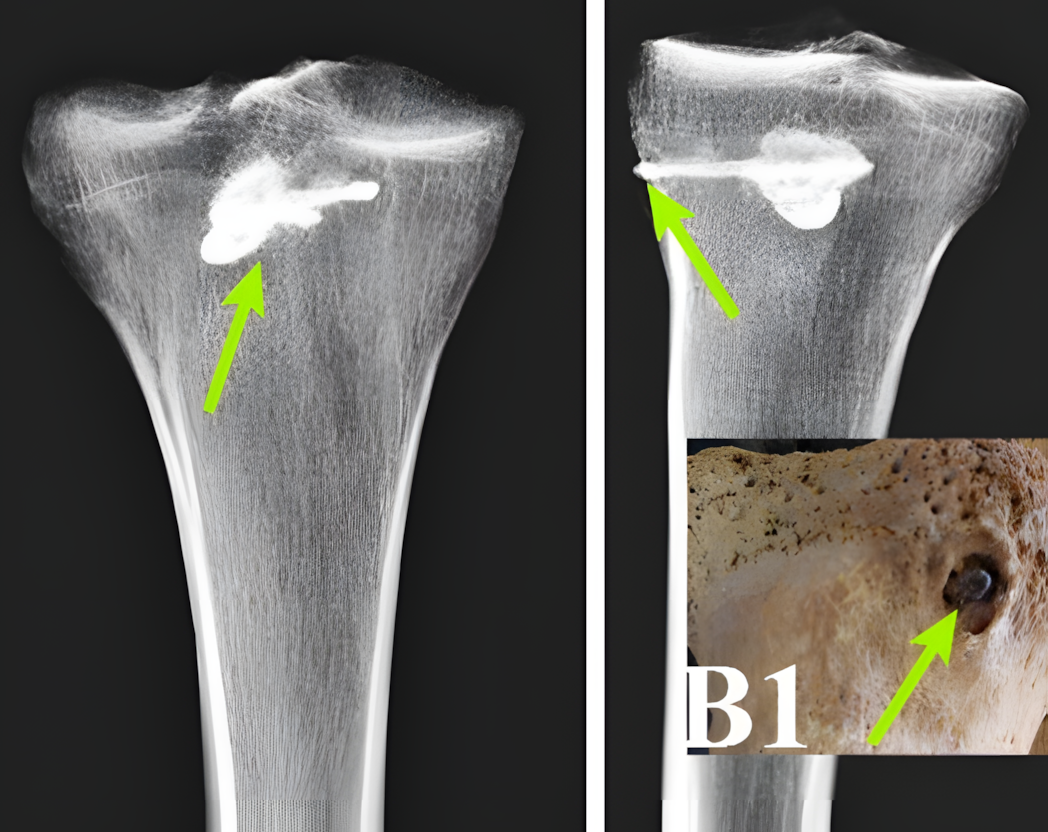

연구진은 X선 형광 분석, 양자계 분석, CT 스캔 등 최첨단 기술을 활용하여 전사의 오른쪽 정강이뼈에 박힌 금속 물체를 확인했다.

이 물체는 길이 44mm, 너비 15mm의 정교한 삼날 금속 화살촉으로, 알려진 다른 파르티아 무기들과 일치했다.

뼈 분석 결과 박힌 화살촉 주변에서 명확한 치유 흔적이 발견되었다.

이물질 주변에 치밀한 뼈 조직이 형성되기 시작하여 전사가 초기 외상에서 살아남았고 그 후 상당 기간 생존했음을 시사한다.

그러나 관통 부위 바로 밖에서는 감염이나 새로운 뼈 형성의 흔적이 발견되지 않았다.